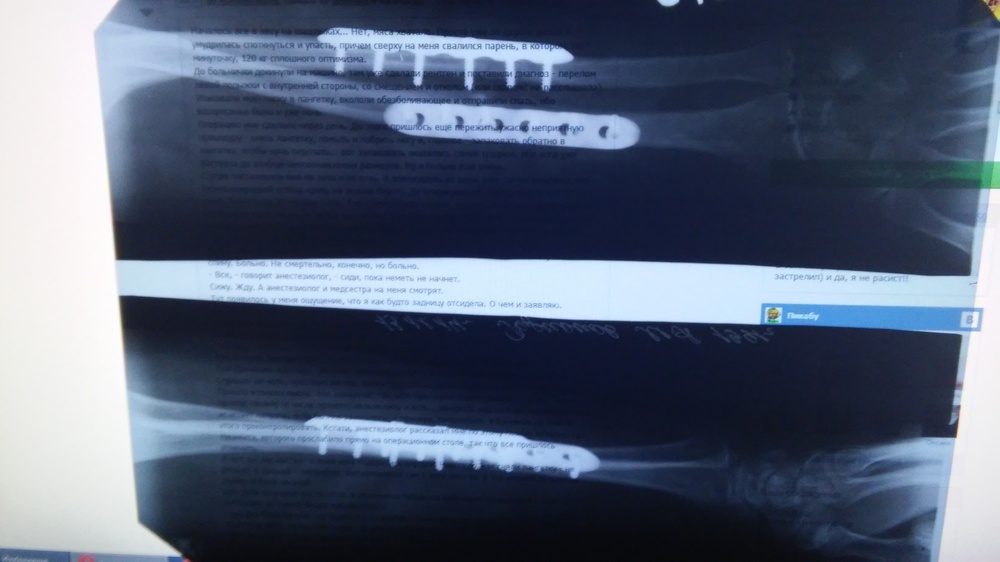

Автор поста оценил этот комментарий

В прошлом году, упав с велосипеда, точно так же поломал себе предплечье. Аппарат Илизарова не ставили, вместо него пластины. Ничего не платил. Лишь после отблагодарил хирурга и медсёстер.

Иллюстрация к комментарию